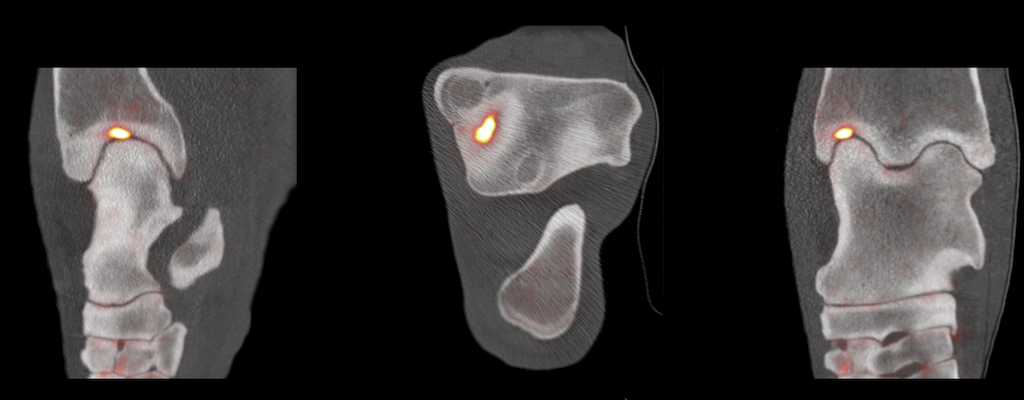

Positron Emission Tomography (PET) is a powerful molecular imaging technique commonly used in human medicine. Our mission is to deliver the full power of PET to the equine veterinarians by designing PET imaging devices meeting unique needs of this unique community.

MILE-PET® is the only PET device for imaging of limbs in standing, lightly sedated horses without anesthesia.

Molecular imaging with PET is now available in a standing sedated equine patient

Since 2015, we have worked with top researchers to establish the science behind equine PET